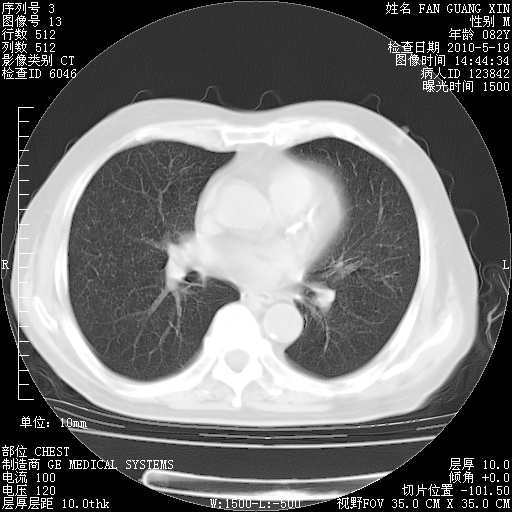

可改为口服强的松40-50mg/d治疗,若病情仍稳定,胸部阴影不再吸收可逐渐减量